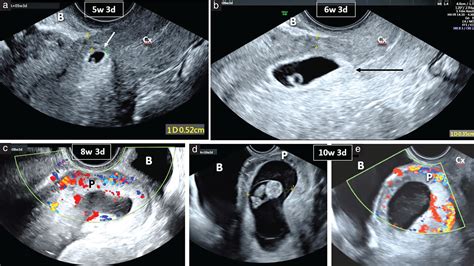

When a physician suspects an ectopic pregnancy, they often perform a transvaginal ultrasound. This procedure uses a specialized wand to provide a high-resolution view of the reproductive organs. By visualizing the uterus, ovaries, and the surrounding areas, radiologists and OB/GYNs look for specific clinical markers.

When doctors look for an ectopic pregnancy by ultrasound, they are essentially looking for an "empty" uterus where there should be a pregnancy sac. The diagnostic process typically involves:

• Identifying the Gestational Sac: In a healthy pregnancy, an intrauterine gestational sac should be visible by the time the human chorionic gonadotropin (hCG) levels reach a certain threshold.

• 6 week ectopic pregnancy ultrasound

• 5 week ectopic pregnancy ultrasound

• types of ectopic pregnancy ultrasound

• 10 week ectopic pregnancy ultrasound